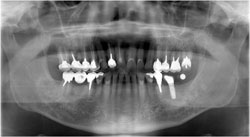

埋入直後のレントゲン写真です。

術前のシュミレーションの通りのインプラントが埋入できました。